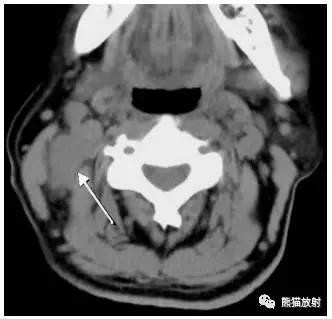

女性,56岁,箭头显示右侧颈部ⅡA区转移性低分化癌。

女性,45岁,淋巴瘤。黑箭显示双侧ⅡB区淋巴结。